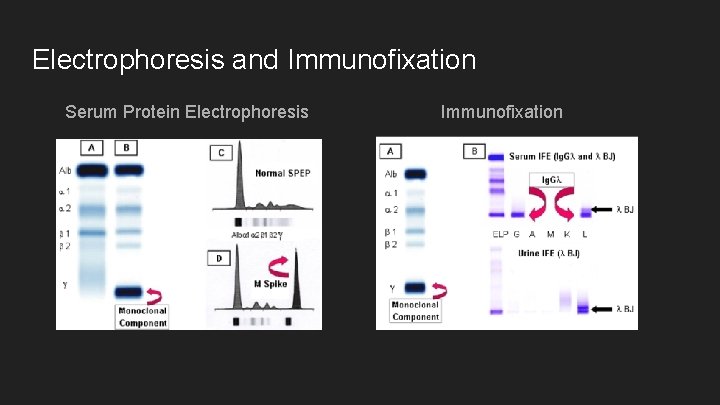

Electrophoresis and Immunofixation Serum Protein Electrophoresis Immunofixation